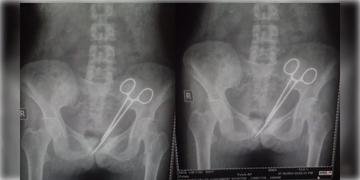

Read more about - Sikkim | ১২ বছর ধরে মহিলার পেটে সার্জিকাল কাঁচি! চিকিৎসকের গাফিলতিতে চরম ক্ষোভ

Sikkim | ১২ বছর ধরে মহিলার পেটে সার্জিকাল কাঁচি! চিকিৎসকের গাফিলতিতে চরম ক্ষোভ